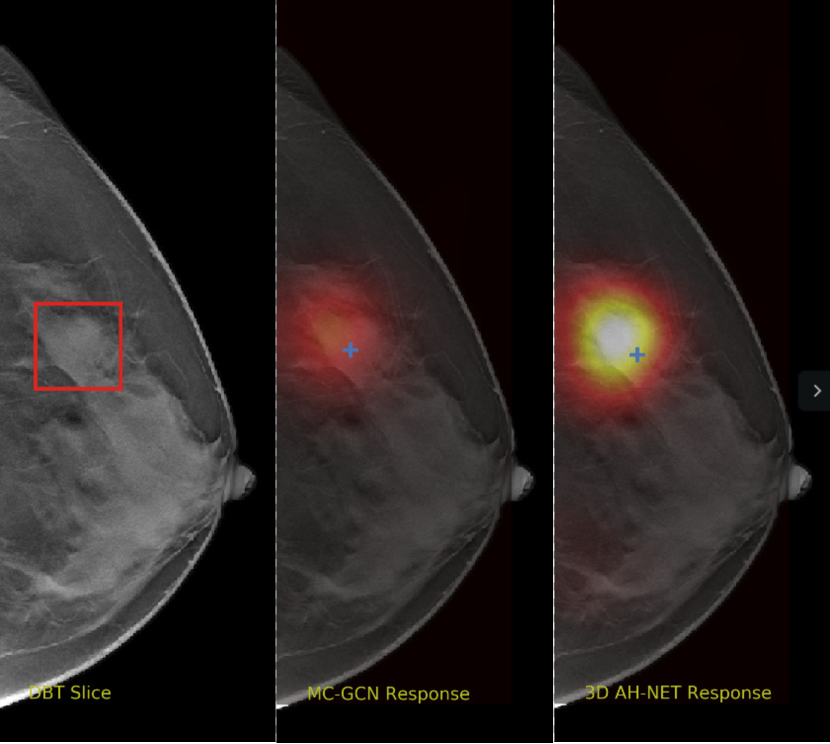

Refer to caption

Figure 5: The visual comparisons of the network responses on 2 different DBT volumes from 2D GCN and the 3D AH-Net with the encoder weights transferred from it. Each volume is visualized with the maximum intensity projection of the xy𝑥𝑦xy plane (top-left), the xz𝑥𝑧xz plane (bottom) and the yz𝑦𝑧yz plane (right). The ground truth lesion centres are shown on the left. With the additional AH-Net Decoders, 3D AH-Net could effectively detect the missing lesion in the first volume (upper row) and remove the false positives in the second volume (lower row).

Non-maximal suppression is performed on the network output map to obtain the lesion locations. The network responses at the local maximal voxels are considered as the confidence scores of the cancerous findings. Fig. 5 shows some visual comparison of the networks output.

We selected some example slices from the DBT dataset to demonstrate the advantage of our proposed AH-Net for the Breast cancer screening. From Fig. 8 to Fig. 12, we show slices from five test DBT volumes that both the MC-GCN and the proposed 3D AH-Net could successfully detect the suspected breast lesion. The original DBT slice is shown on the left with the lesion annotated by our radiologist. Please note the original annotation is a 3D box. The figures in the middle and on the right are response maps from MC-GCN and 3D AH-Net overlaid on the original image, respectively. The detection locations obtained with non-maximal suppression are displayed with cross markers. As shown in the images, the proposed network can detect breast lesions varying in sizes and appearances. The confidence of the 3D AH-Net is usually higher than that of MC-GCN. From Fig. 13 to Fig. 17, we show five volumes that MC-GCN failed to detect the lesions since the lesions were not distinguishable from other breast tissues using the information within the slice. In contrast, 3D AH-Net was able to detect the lesions from such volumes using the 3D context between slices. As shown in Fig. 18 to Fig. 22, there are also volumes with lesions that both network failed to detect. Such lesions normally reside in the dense breast tissues. The boundary between these lesions and the normal breast tissues usually have low contrast. The networks sometimes also confuse them with other roundish structures in the breast such as lymph nodes or skin moles.

Figure 8: Example DBT slice 1 with a lesion that can be detected by both MC-GCN and 3D AH-Net. Though the lesion is blended in the dense breast tissues, our network is able to detect it according to the speculations around the lesion boundary.